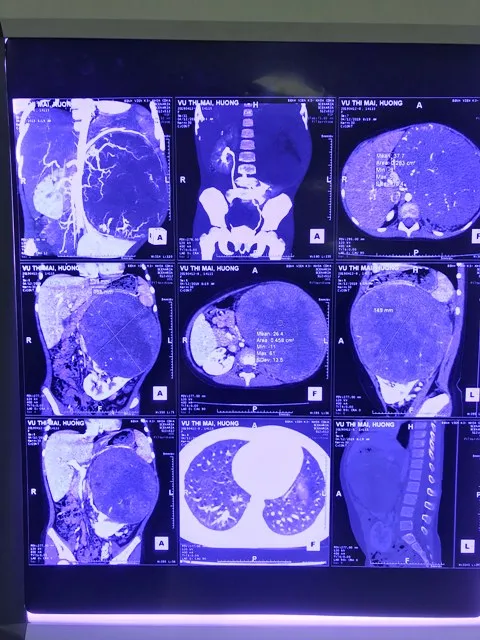

Phẫu thuật thành công khối u thận “khủng” ở bé gái 6 tuổi ảnh 1 Hình ảnh chụp phim khối u lớn chèn ép nhiều bộ phận trong ổ bụng

Ngày 27-6, Bệnh viện K cho biết các bác sĩ của bệnh viện mới đây đã phẫu thuật loại bỏ thành công khối u thận cho một bệnh nhi nữ mới 6 tuổi. Bác sĩ Đoàn Trọng Tú, Trưởng khoa Ngoại bụng 2 cho biết, bệnh nhi là cháu Vũ Thị Mai H. (6 tuổi, ở Nghệ An) được đưa bệnh viện khám với chẩn đoán ban đầu là u sau phúc mạc. Sau khi thăm khám và chụp chiếu, các bác sĩ phát hiện bệnh nhi có khối u lớn khoảng 20 cm, chèn ép nhiều bộ phận gây đau tức, ảnh hưởng lớn đến hô hấp cũng như sinh hoạt của bệnh nhi H.

Xác định đây là ca bệnh khó, các bác sĩ Khoa Ngoại bụng 2 và Khoa Nhi đã hội chẩn, dựa trên triệu chứng lâm sàng, yếu tố dịch tễ, phim chụp cắt lớp vi tính, mô bệnh học và kết quả hóa mô miễn dịch đã xác định bệnh nhi H. bị u nguyên bào thận trái (u Wilm) và thống nhất phác đồ điều trị hóa chất bổ trợ trước mổ và sau đó tiến hành phẫu thuật.

Sau khi kết thúc điều trị bổ trợ trước, khối u chỉ đáp ứng một phần (kích thước u giảm ít, một phần trung tâm hoại tử) nên phẫu thuật là phương pháp tối ưu nhất với bệnh nhi H. Với sự chuẩn bị kỹ càng và kinh nghiệm của êkíp phẫu thuật, sau gần 3 giờ căng thẳng, khối u có đường kính 20cm, nặng khoảng 2kg đã được cắt bỏ khỏi cơ thể bệnh nhi H.